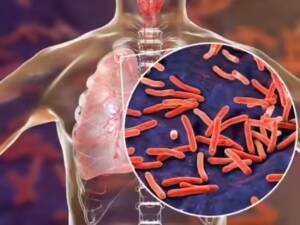

Sputum microscopy and tuberculosis

Sputum smear microscopy has been the primary method for diagnosis of pulmonary tuberculosis in low- and middle-income countries, which is where nearly 95 per cent of TB cases and 98 per cent of deaths due to TB occur.

It is a simple, rapid and inexpensive technique which is highly specific in areas with a very high prevalence of tuberculosis.

It also identifies the most infectious patients and is widely applicable in various populations with different socio-economic levels. Hence, it has been an integral part of the global strategy for TB control.

However, sputum smear microscopy has significant limitations in its performance. The sensitivity is grossly compromised when the bacterial load is less than 10,000 organisms/ml sputum sample. It also has a poor track record in extra-pulmonary tuberculosis, pediatrics tuberculosis and in patients co-infected with HIV and tuberculosis.